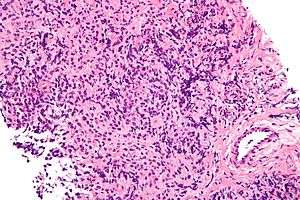

| Micrograph of a primary mediastinal large B-cell lymphoma, a type of large-cell lymphoma. H&E stain. | |

One classification system for lymphomas divides the diseases according to the size of the white blood cells that has turned cancerous. The large-cell lymphomas have large cells. A large cell, in this context, has a diameter of 17 to 20 µm.[1] Other groups of lymphomas in this system are the small-cell lymphomas and mixed-cell lymphomas.